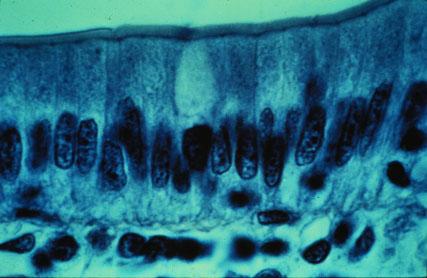

I-29 (5) K Slide 5. Observe microvilli of columnar-shaped cells. A goblet cell is in the center containing mucus (light-staining).